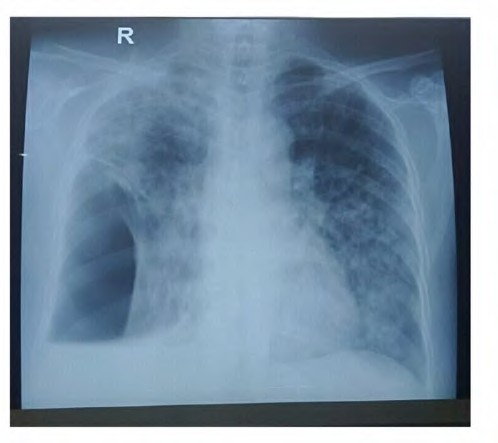

Gambar 1. Gambaran foto toraks pada pasien pneumotoraks sekunder akibat TB paru menggambarkan adanya pneumotoraks di sebelah kanan bawah paru dengan luas menurut kriteria Light sebesar >20%, infiltrat yang sudah menyebar luas di paru kanan dan paru kiri bawah.